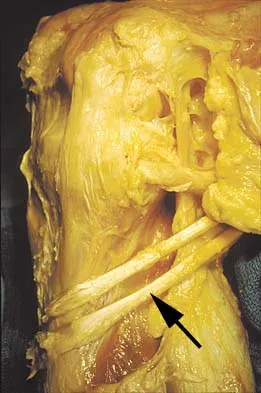

Figure 11 shows the anatomic dissection of the medial side of the knee joint after removal of the superficial fascia. The arrow is pointing to what structure?

Explanation

The semitendinosus and gracilis tendons lie beneath the superficial fascia and superficial to the medial collateral ligament. The semitendinosus is located more inferior to the gracilis tendon. The sartorius is more posterior and distal as is the medial collateral ligament. The semimembranosus is posterior. Pagnani MJ, Warner JJ, O'Brien SJ, Warren RF: Anatomic considerations in harvesting the semitendinosus and gracilis tendons and a technique of harvest. Am J Sports Med 1993;21:565-571.